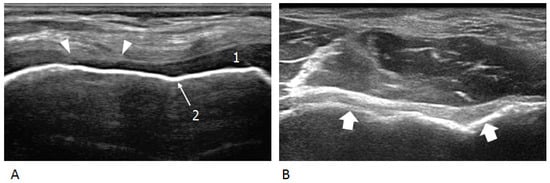

2. Ultrasound and Disease Activity

3. Ultrasound and Osteochondral Damage